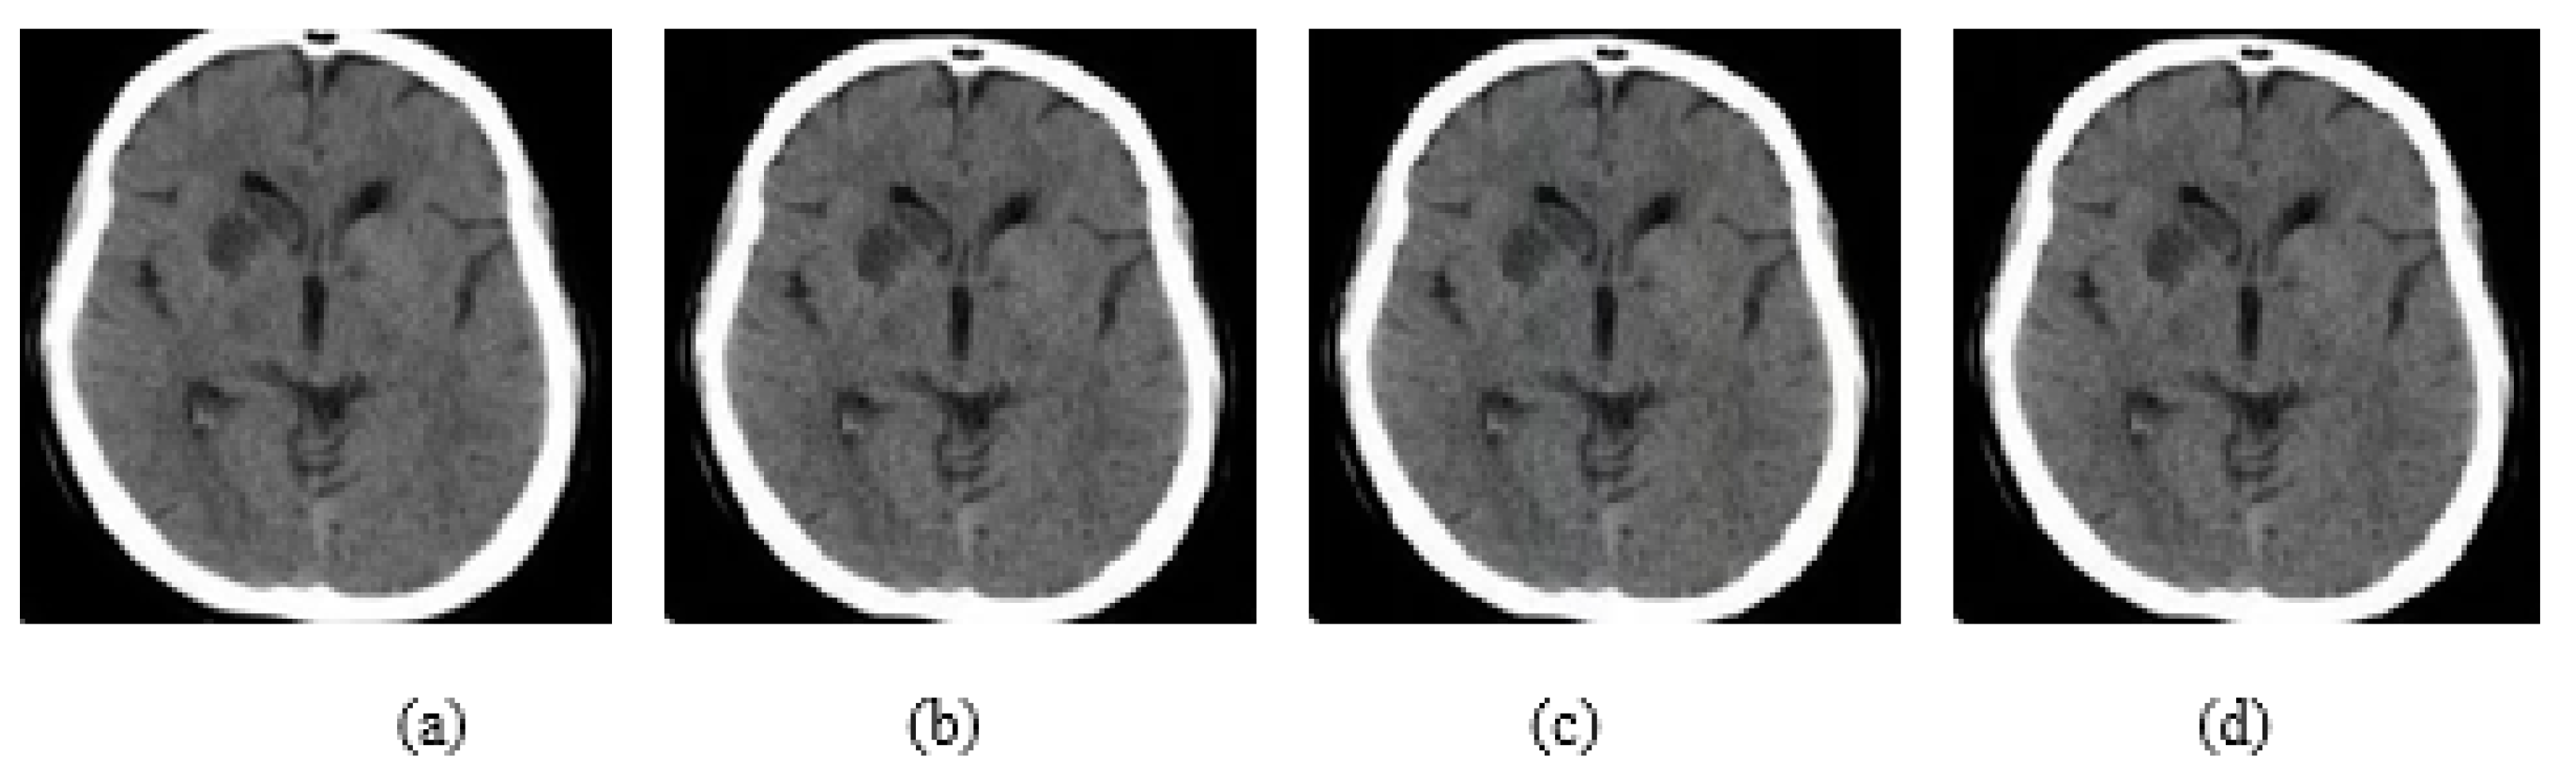

In addition, experiments were performed with FGSM, PGD, and Square Attack for ϵ values equal to 0.01, 0.03, 0.05, 0.07, 0.09, 0.12, and 0.15. In Figure 6, MRI with aforementioned attacks and ϵ = 0.01 are presented. The human eye cannot understand any difference between these images. In Figure 7, attacks with ϵ = 0.07 are depicted. Square Attack causes the biggest distortion compared to FGSM and PGD. However, small changes can be observed also in the other two attacks. In Figure 8, the ϵ value has been increased to 0.15, making the noise perceptible.

Figure 6.

(a) Initial Image, (b) FGSM attack with ϵ = 0.01, (c) PGD attack with ϵ = 0.01, (d) Square Attack with ϵ = 0.01.

Figure 7.

(a) Initial Image, (b) FGSM attack with ϵ = 0.07, (c) PGD attack with ϵ = 0.07, (d) Square Attack with ϵ = 0.07.

Figure 8.

(a) Initial Image, (b) FGSM attack with ϵ = 0.15, (c) PGD attack with ϵ = 0.15, (d) Square Attack with ϵ = 0.15.